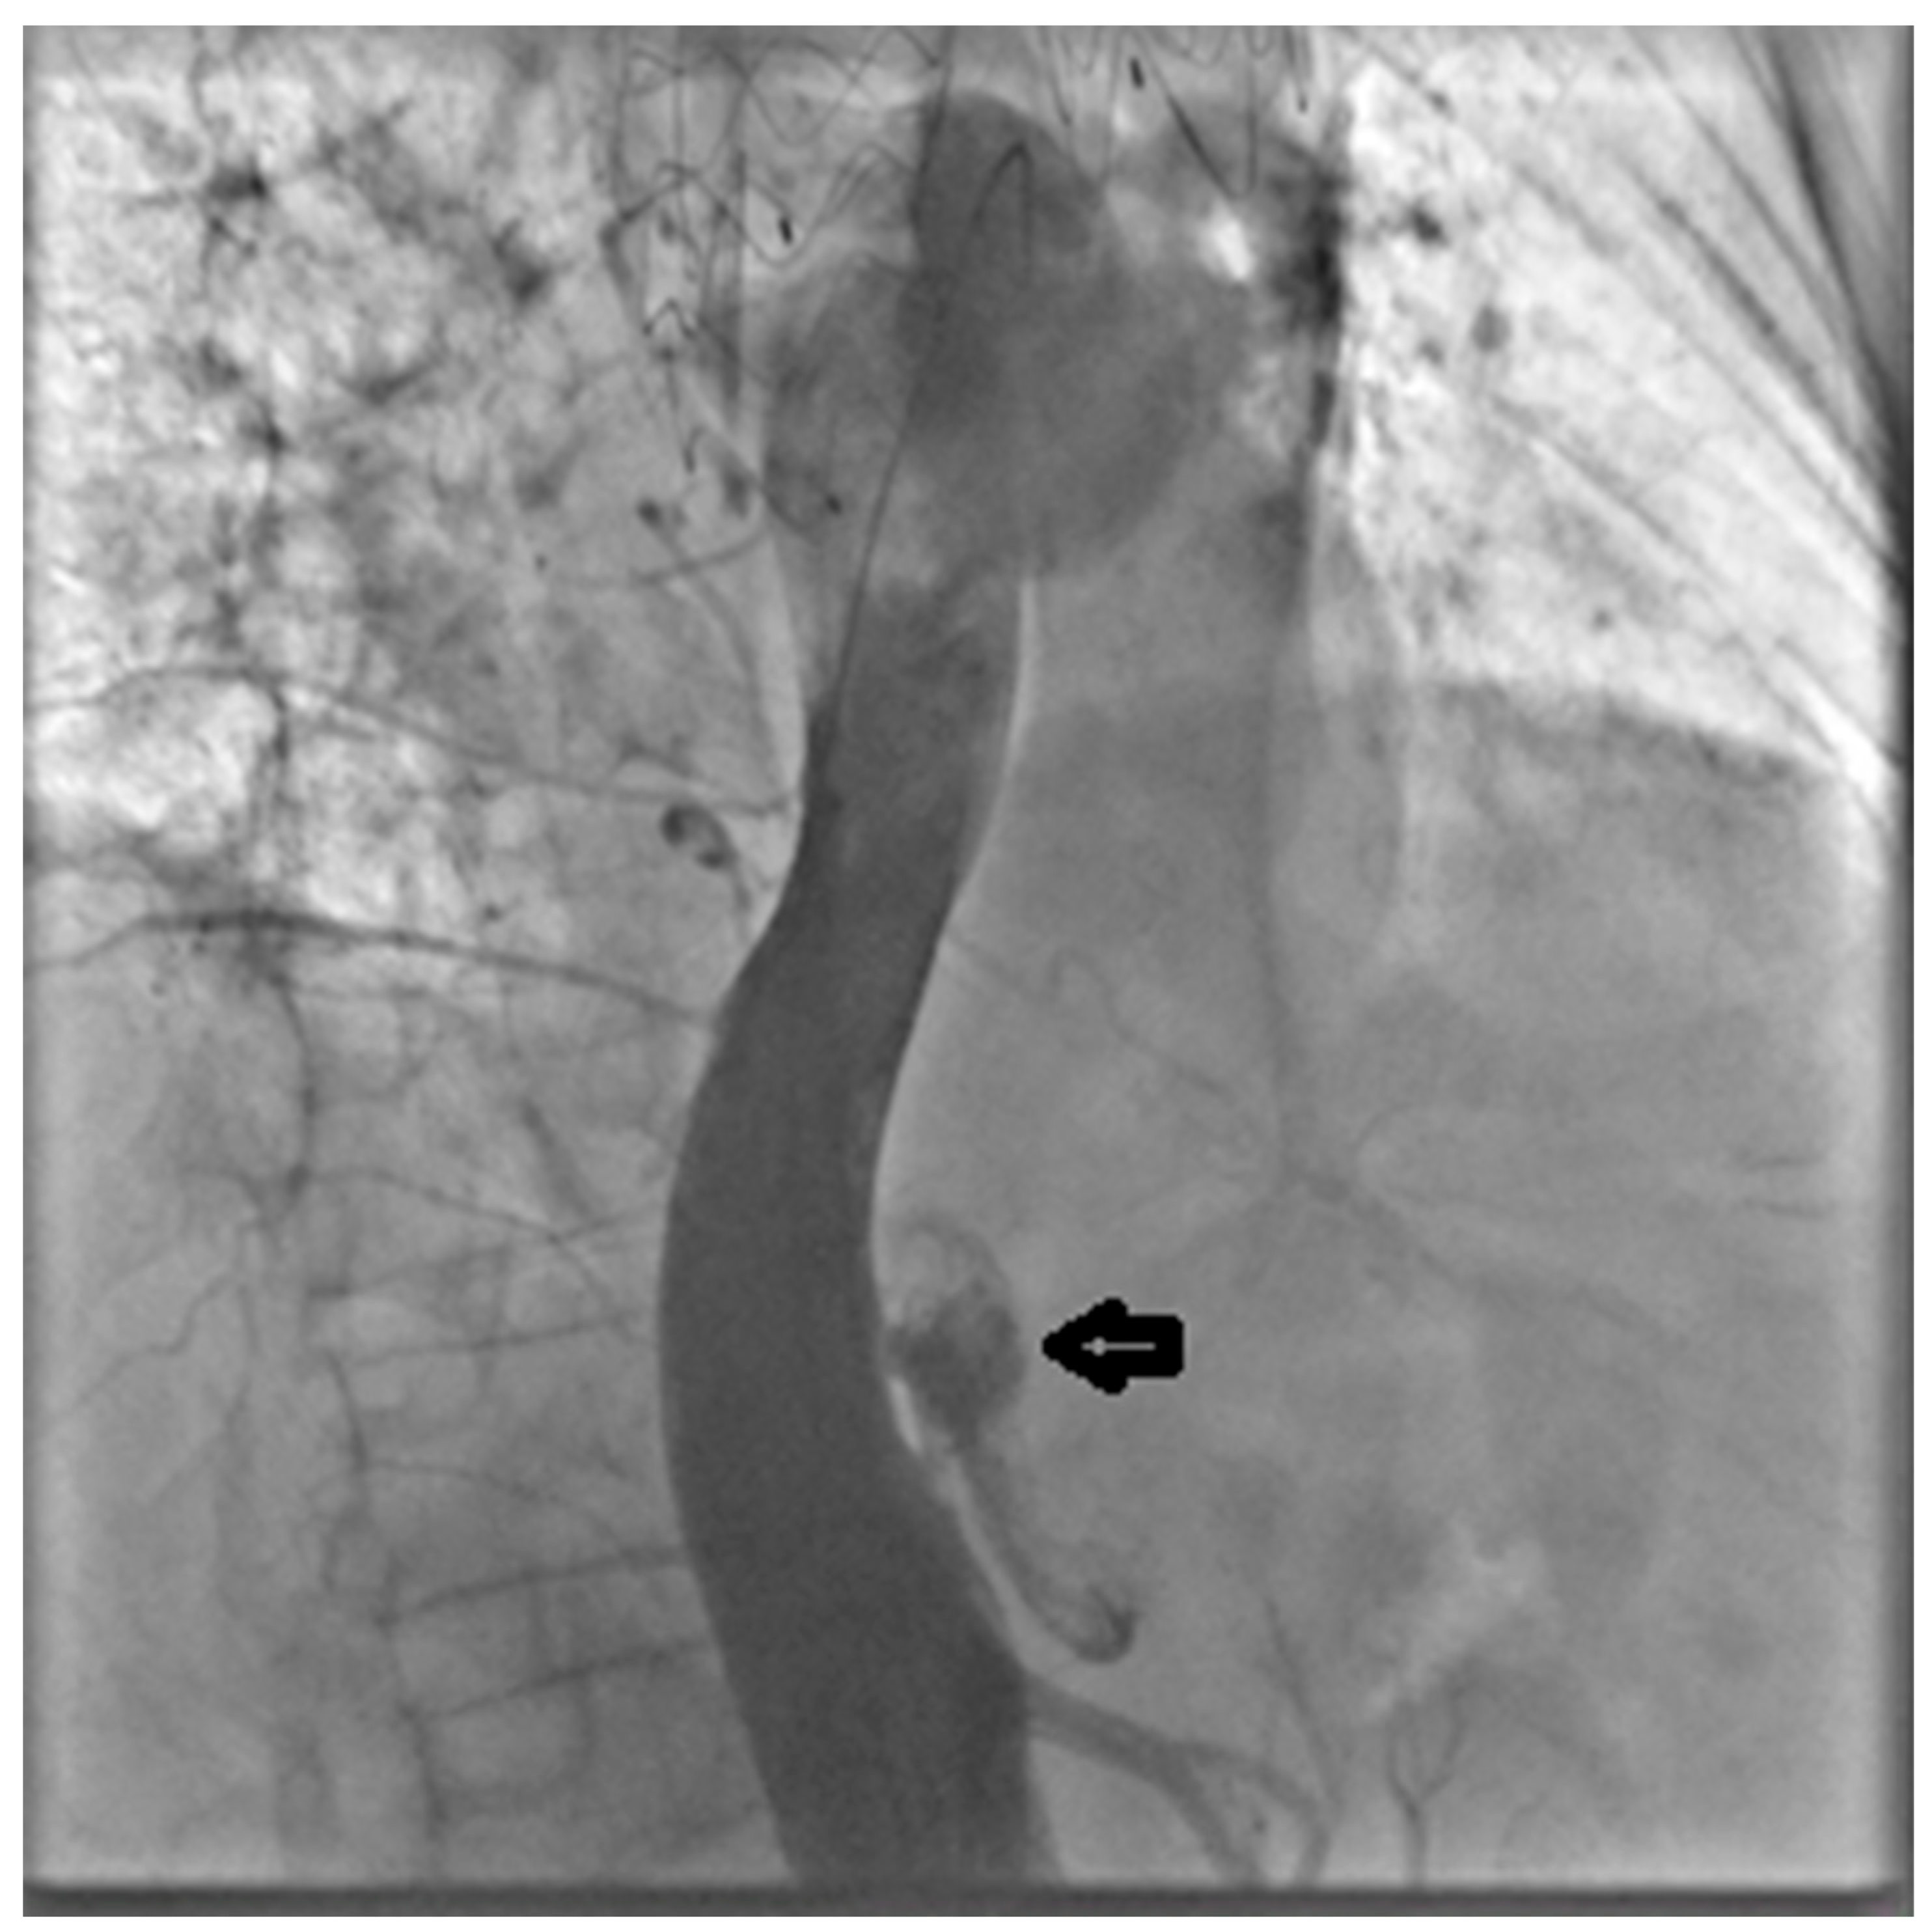

Through the LCFA, a 6F pigtail catheter was advanced into the thoracoabdominal aorta. Intraoperative angiography confirmed substantial FL dilation and two distal re-entry tears beyond the prior TEVAR, with clear retrograde backflow (Figure 2).

Figure 2.

Intraoperative angiography with injection into the true lumen demonstrating marked false lumen dilation with evidence of a distal re-entry tear and retrograde backflow (arrow).